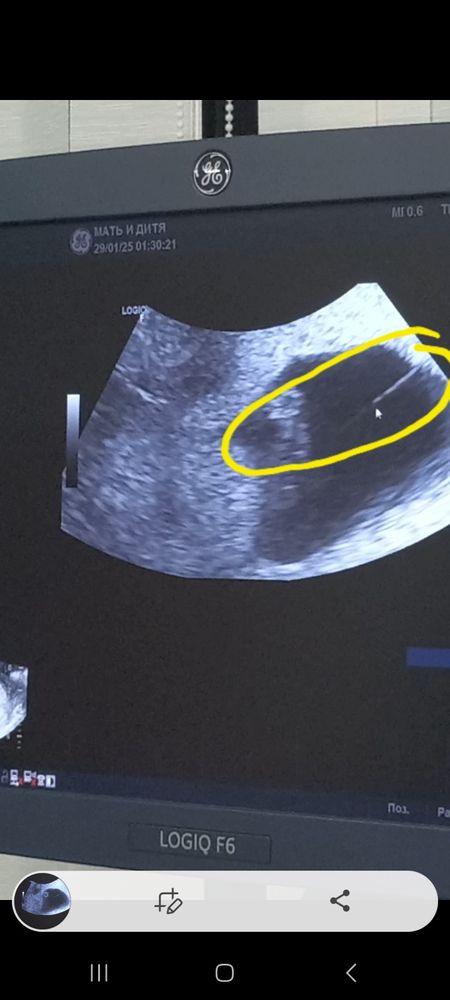

🆘️Тяжи,перегородка в пузыре❗️❗️❗️🆘️.Кто сталкивался с амниотическими тяжеми поделитесь как у вас все протекает и у кого какие последствия ?10 дней назад была

🆘️Тяжи,перегородка в пузыре❗️❗️❗️🆘️.Кто сталкивался с амниотическими тяжеми поделитесь как у вас все протекает и у кого какие последствия ?10 дней назад была на узи и увидели в пузыре ниточку.Врач на неё внимание обратила но как буд-то ничего страшного,типо фигня.Вчера опять на узи мы увидели эту полосочку ,врач уже прям смотрела её внимательн